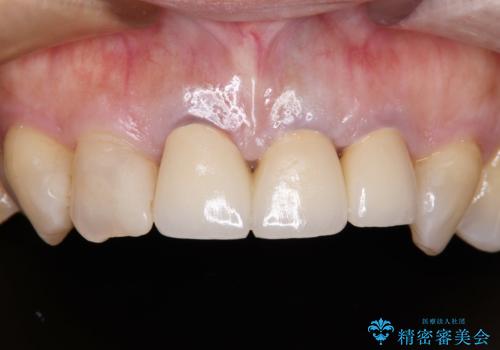

- 黄色みのある前歯のセラミックを、明るい色に替えたいとのことで来院された患者様です。

透明感がないことも気になっていたため、オールセラミッククラウンでは透けてしまう可能性のある金属の土台をファイバーコアに置き換え、1トーン明るいクラウンにて仕上げていくこととしました。

透明感のある自然な色合いとなり、患者様には大変満足していただけました。